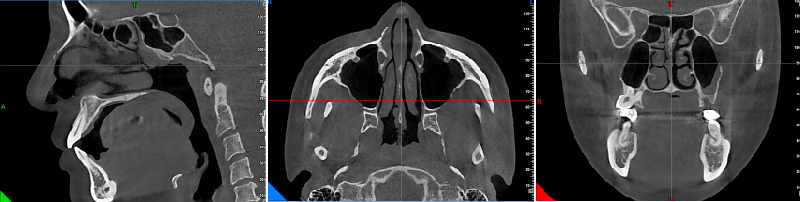

精準3D電腦斷層影像輔助系統

施行鼻整形手術前,由醫師評估如需進行3D電腦斷層掃描完整分析鼻部結構,將可能的病灶以及建議改善的空間。

術前全面性的評估與深度溝通細節,是韋志曄醫師一貫的要求。